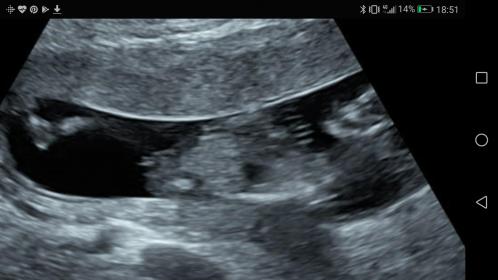

Hi all! I just had my 12 week scan at 12w5d and the tech seemed quite convinced it was a girl (much to my complete surprise because I was sure I'd just have another boy). I've been researching a bit and it definitely seems girly but is it too early to tell really? Is there a chance it will rise? Attachment 39149